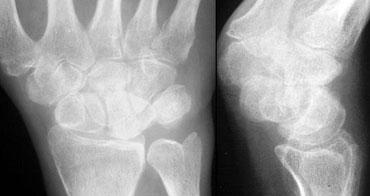

Phân tích:

1. Gãy xương thuyền và mỏm trâm trụ.

2. Cung I và II bị gián đoạn tại khớp LT (nguyệt-tháp).

3. Có sự song song giữa xương nguyệt và cực gần xương thuyền với xương quay.

4. Xương thuyền bị ngắn lại (foreshortened), cho thấy nó đang nghiêng và di chuyển về phía lòng bàn tay.

5. Tất cả các xương cổ tay còn lại đều có tính song song, ngoại trừ xương nguyệt, cực gần xương thuyền và xương quay.

Mặc dù đây có thể là trật khớp quanh nguyệt, nhưng chỉ dựa vào tư thế PA rất khó để phân biệt đây là trật khớp xương nguyệt hay trật khớp quanh nguyệt. Hình dạng tam giác của xương nguyệt có thể là kết quả của việc chỉ nghiêng đơn thuần hoặc trật khớp kèm nghiêng.

Trật khớp quanh nguyệt kèm gãy xương thuyền và mỏm trâm trụ. Đầu mặt lòng của xương nguyệt cũng bị gãy (xem vòng tròn).

Cùng ca lâm sàng với tư thế nghiêng được hiển thị thêm.

Bây giờ chúng ta thấy rõ ràng đây là trật khớp quanh nguyệt.

Vì vậy, hình dạng tam giác của xương nguyệt là kết quả của việc nghiêng đơn thuần.

Trên tư thế nghiêng, quan sát thấy gãy đầu mặt lòng của xương nguyệt. Do đó, bệnh nhân này có nguy cơ trật khớp tái phát.